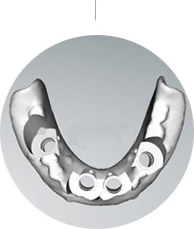

微创即刻种植技术是专门针对东方人群的口腔环境及牙齿、牙骨的特性精研多年的齿科精艺,具有显著的“快准精微恒”的特性,获得口腔“诺贝尔奖”是世界亚洲人群的植牙精艺!

殷先生的牙齿状况比较特殊:上排牙骨比下排本身就窄,上牙槽骨还缺牙30多年,废用性萎缩非常严重。此前预约了很多口腔医院,普通的种植牙技术恐怕很难实现上面半口种植,并且在咬合和美观度方面也无法达到预期效果!郑苍尚院长综合考虑目前牙齿具体情况为殷先生推荐all-on-4(种植4颗即能恢复半口牙)手术方案......

由于严重的牙周病,他的上半口牙齿全掉光了,下牙也缺了一颗,硬的、粘的、肉类都没法吃。蒋先生在女儿的陪同下到麦芽口腔口腔看牙,接受了麦芽口腔的即刻负重种植牙手术,通过创新性地应用拱形受力原理,仅植入4颗种植体,达到12~14颗牙的修复效果,马上戴上临时牙冠,恢复咀嚼......